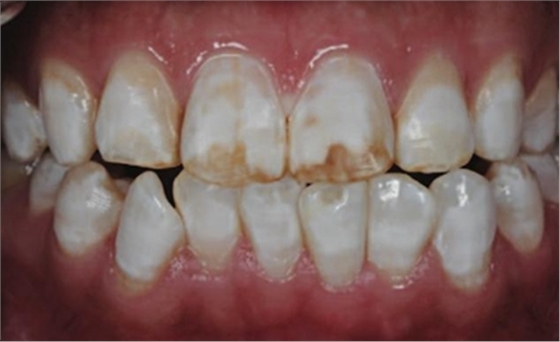

一28歲女性患者來我院修復(fù)科就診,主訴為前牙嚴(yán)重的牙齒著色和缺損十余年,要求改善牙齒的美觀。臨床檢查表明該患者有重度氟斑牙,極大的影響了前牙美學(xué)。

考慮到患者為年輕人,保守治療方法比傳統(tǒng)侵入性治療手段更為合適。術(shù)前牙周治療預(yù)防牙齦炎癥和改善牙齦健康狀態(tài),隨后聯(lián)合采用釉質(zhì)打磨、牙漂白和樹脂滲透來處理牙釉質(zhì)表面。